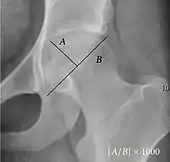

| Reimer's migration index[9] | ![]() |

The percentage of the femoral head that lies outside of the acetabular roof. It is also called the femoral extrusion index. | <25% |